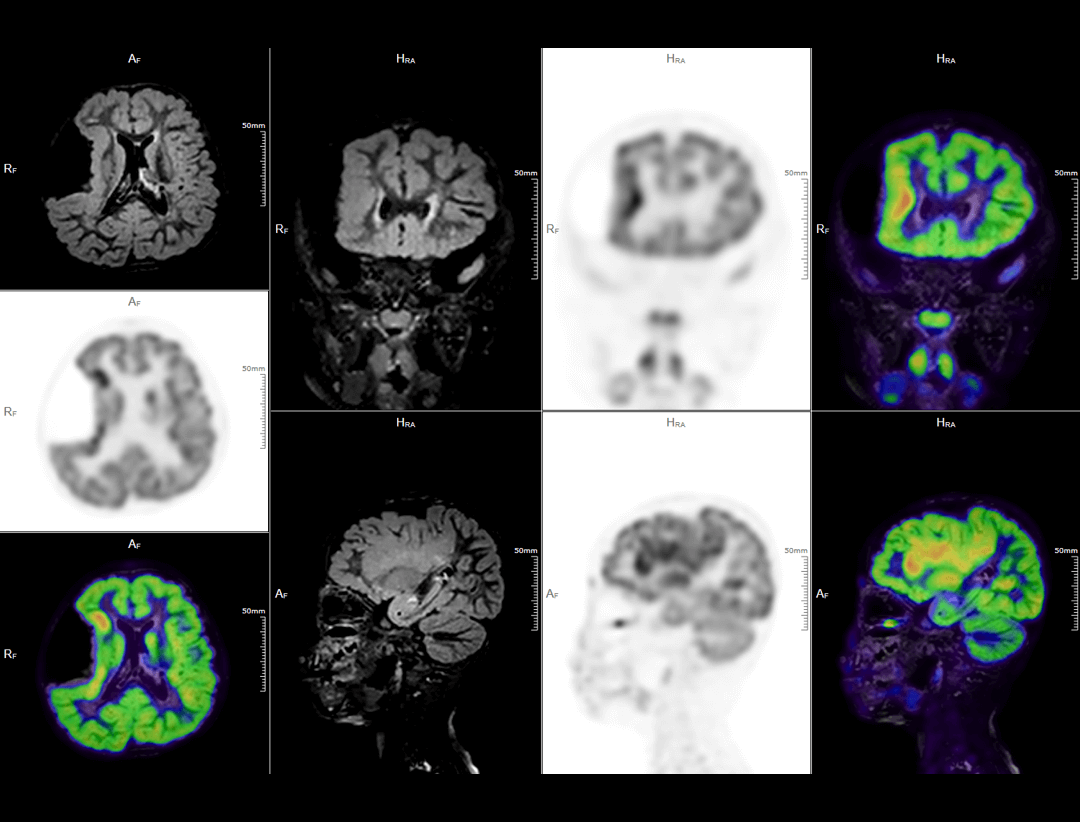

Neuroimagistică

uPMR 790 permite imagistică simultană PET/MRI cu rezoluție temporală și spațială ridicată. Această tehnologie redefinește standardele clinice și de cercetare, oferind imagini anatomice și funcționale în timp real.